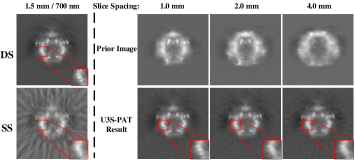

Selecting an appropriate slice spacing is essential to balance the data volume and quality of reconstructed images. To evaluate its impact on image quality, we reconstructed PAT images at different slice spacing and the results are depicted in Fig.8. As can be seen, as the slice spacing increases, the reconstructed images become increasingly blurred and artifacts emerge. The blurring can also be seen in the prior images, which confirms that the feasibility of our U3S-PAT strategy comes from redundant spatial information shared between adjacent slices during spiral scanning.